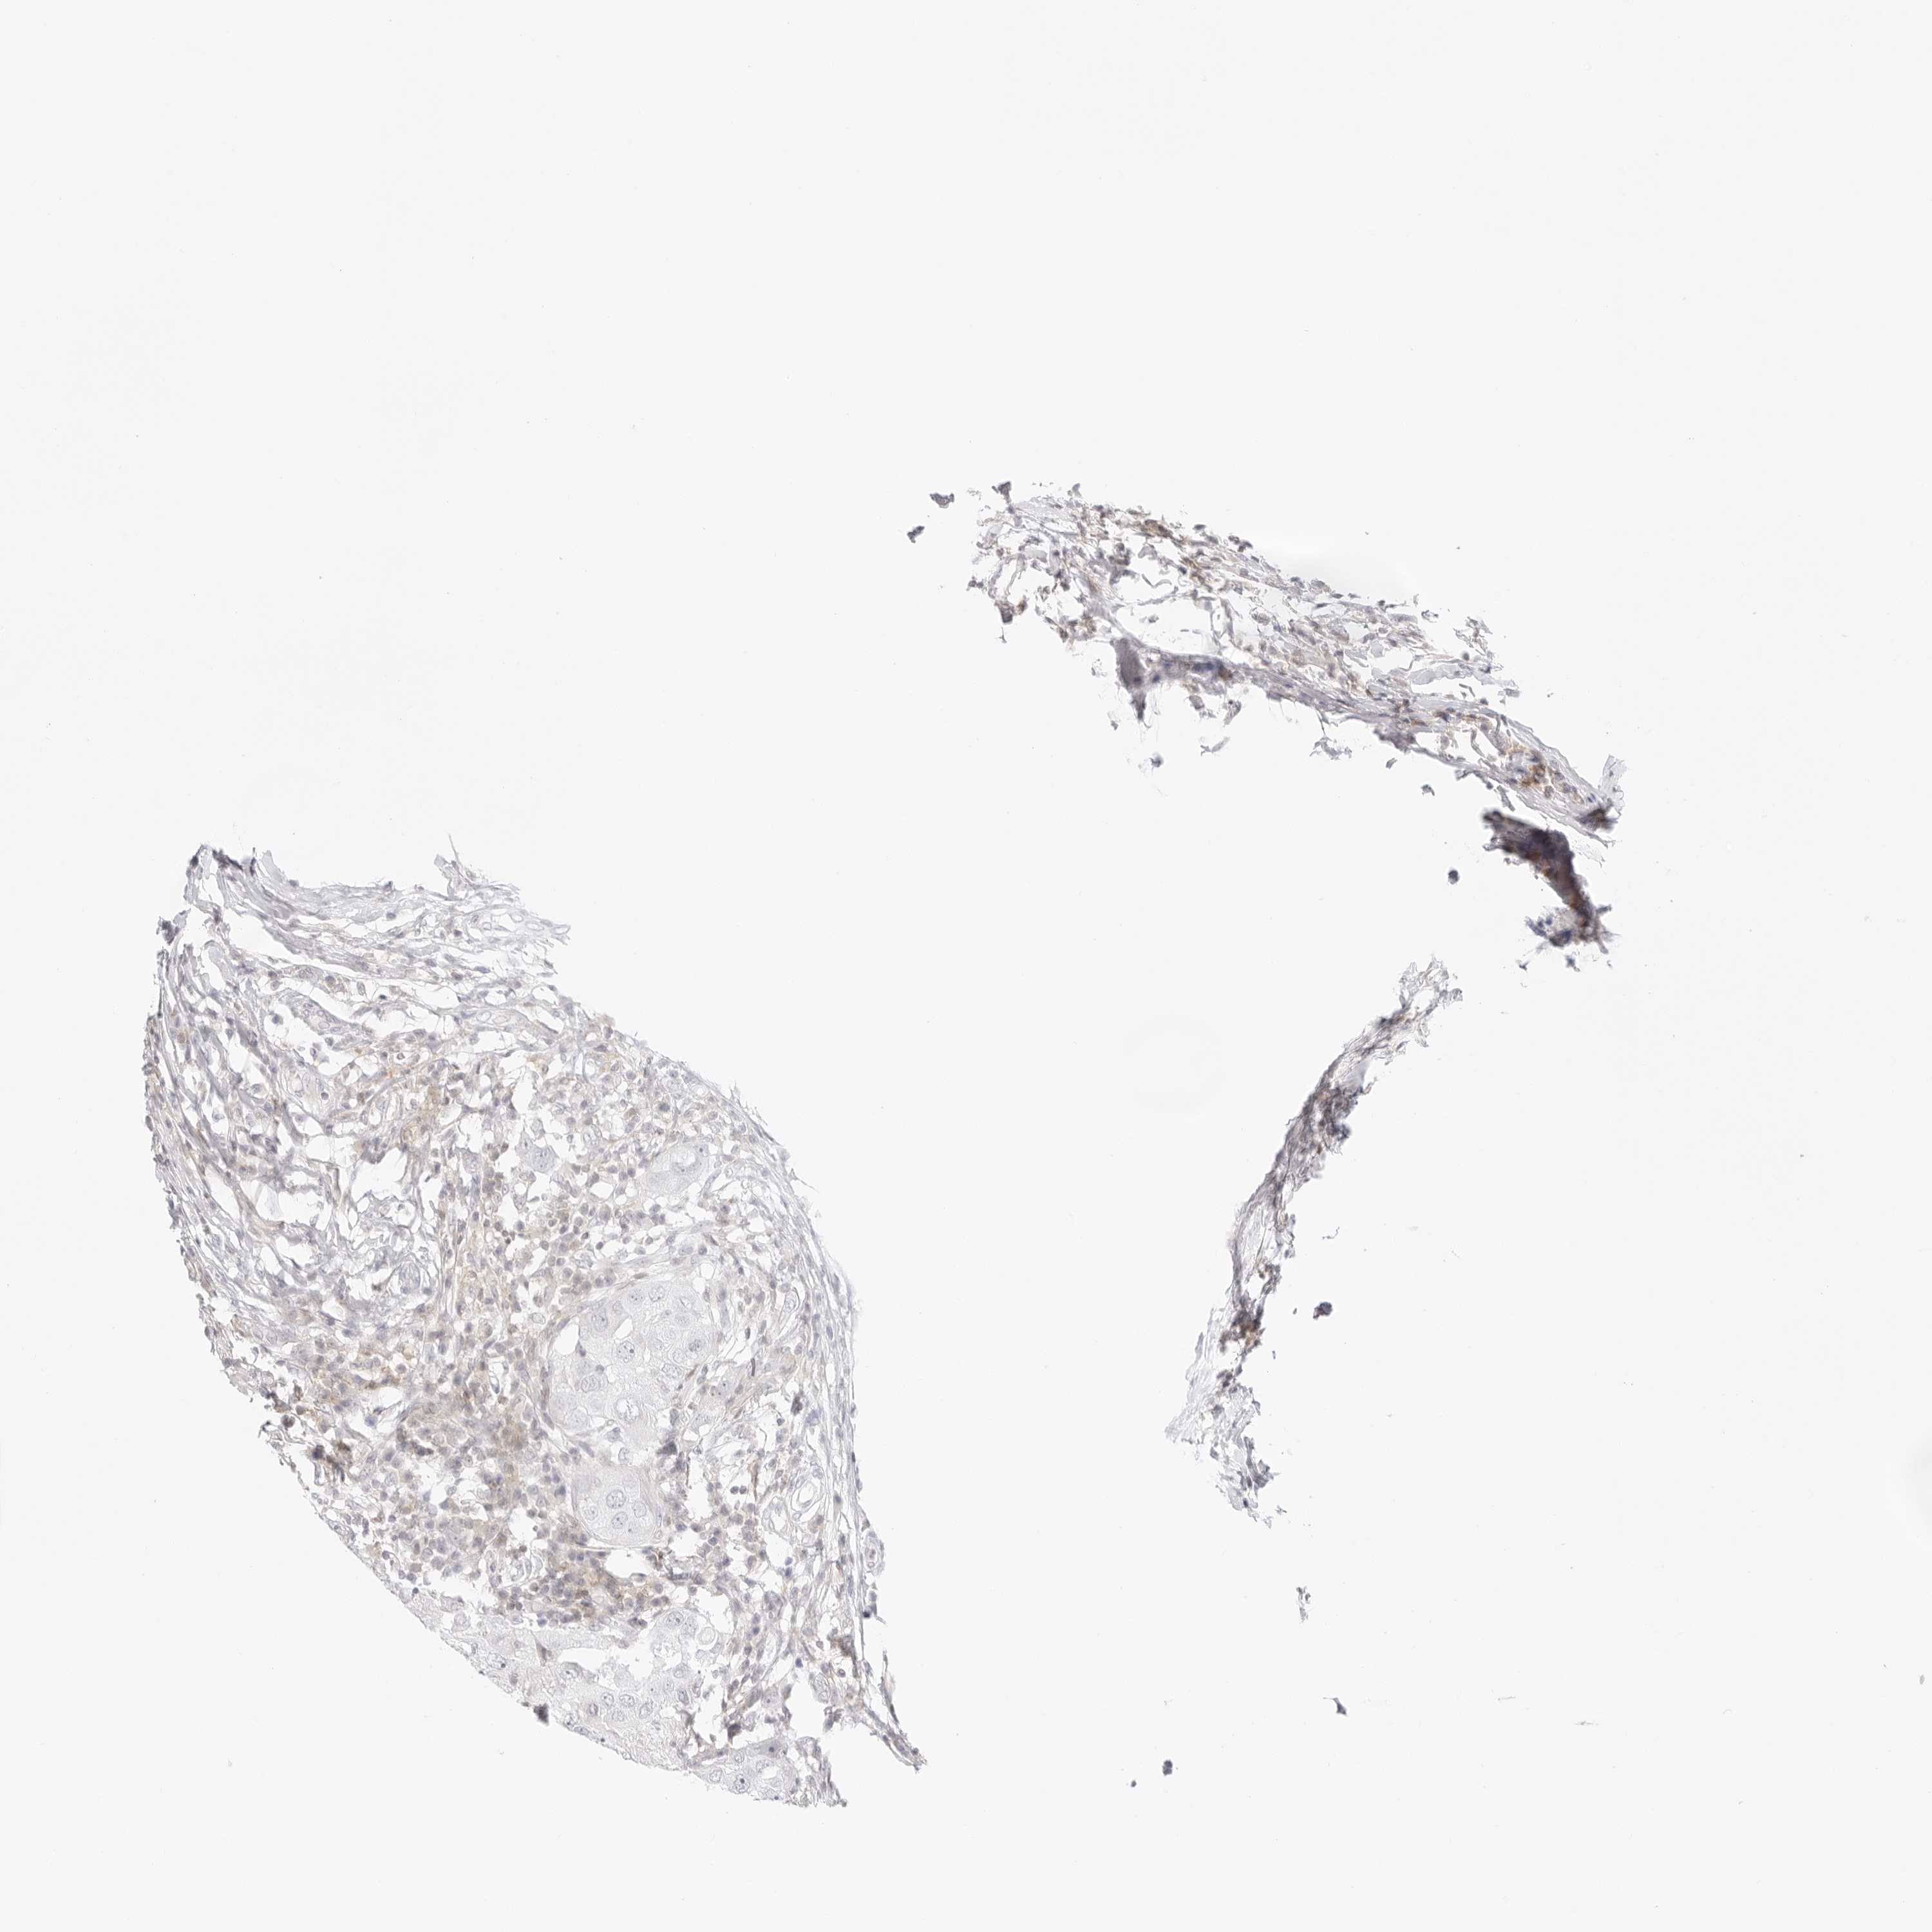

CANCER BREAST CANCER Show tissue menu

BRCA TCGA BRCA VALIDATION PROTEIN EXPRESSION